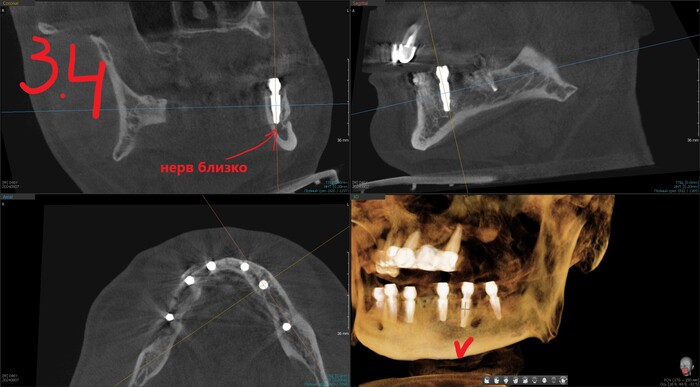

Результат такой - торки получены эталонные везде, кроме двух крайних имплантатов слева (3.4 и 3.6). Но не страшно, сверху зубов-антогонистов нет, нагрузки на протез не будет серьёзной. Да и "всё на 6" прощает подобное.

Имплантолог видит, сколько мм можно докрутить безопасно для структур челюсти (нервов, сосудов). Делает дело.